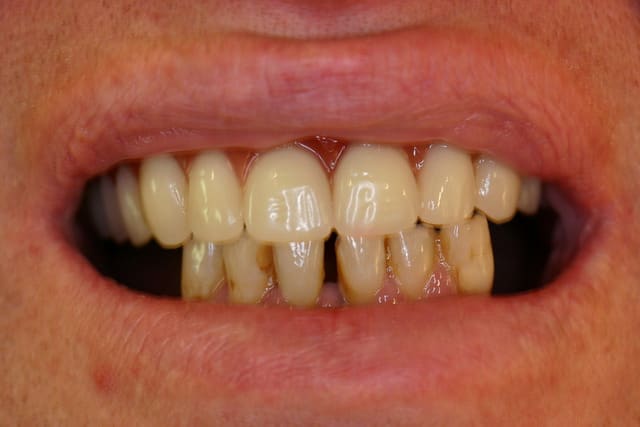

1.Bon... situation pré-extractionelle ( Je crois qu il faillait vraiment extraire )

2. Complet à essai en bouche après extraction et PRFs ds tous les alvéoles puis 3 séances d ostéotensions à venir pour le maxillaire

3. Vue sur articu

4. Télé de profil post-extractionelle

Bon la suite sera ostéotension mandibule et pose des implants mandibulaires en enfoui ds 45 j